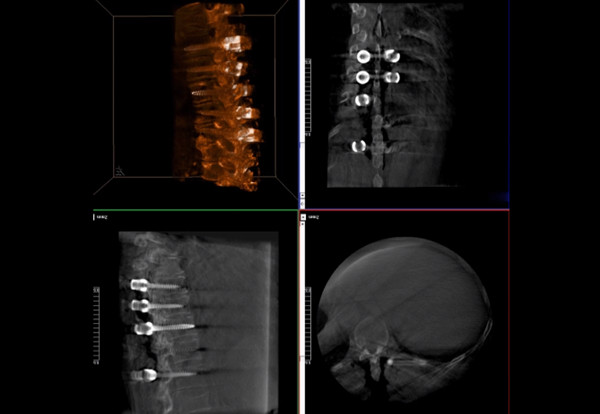

普愛醫(yī)療術(shù)中三維導(dǎo)航C臂快速生成橫斷面、矢狀面、冠狀面斷層圖像和三維立體圖像,方便醫(yī)生確認(rèn)手術(shù)部位。C形臂的大平板帶來出色的顯示視野,可以更好的顯示手術(shù)部位全局情況,確保手術(shù)規(guī)劃及執(zhí)行的準(zhǔn)確性。

三維影像檢驗螺釘植入效果

一臺C形臂

二維三維影像 皆能完好呈現(xiàn)